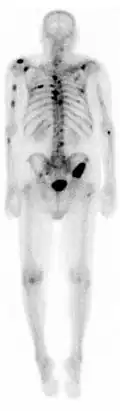

Cintigrafia óssea

Cintigrafia óssea ou gamagrafia óssea é uma técnica de diagnóstico por imagem de medicina nuclear usada para diagnosticar várias condições ósseas, incluindo cancro (primário ou metástase) no osso, osteíte(inflamação do osso), fraturas ou fissuras ósseas (que podem não ser visíveis em imagens de raios X tradicionais) e infecção óssea (como artrite séptica).[1]

A cintigrafia fornece imagens funcionais, permitindo a visualização do metabolismo ósseo ou da remodelação óssea, que técnicas de imagem como tomografia simples e raio X não conseguem. O PET Scan (tomografia por emissão de positrões) também permite imagens funcionais do metabolismo, mas é consideravelmente mais caro.[2]

Injetando 6.3 milisievert (mSv) de Tecnécio 99m as imagens do metabolismo ósseo podem ser obtidas em 2 a 5h depois. Normalmente produz uma imagem anterior e uma posterior, mas pode ser combinado com uma Tomografia computadorizada por emissão de fóton único (SPECT) para maior especificidade.[3]